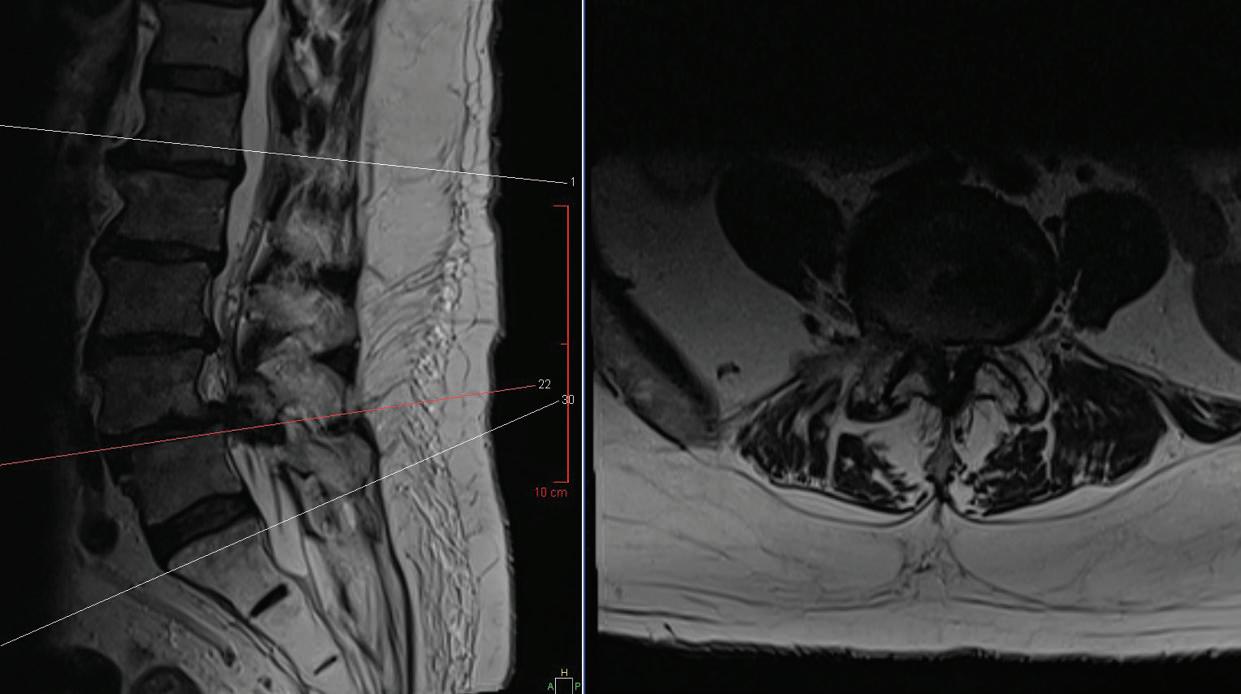

It was time to consider another step: surgery to fix any structural problems. An MRI and X-ray provided a clearer picture of what was going on. Peter’s spine showed signs of severe spinal stenosis. This condition occurs when spaces in the spine become narrowed due to factors such as injury or arthritis, placing pressure on nerves running through the spinal canal.

Matthew McDonnell, MD, a boardcertified orthopedic spine surgeon at RWJUH in New Brunswick, saw Peter’s case as urgent. “The steps we normally start with for symptomatic spinal stenosis—physical therapy, medication, epidural injections—had already been attempted,” he says. “Surgery to fix the structural problem was clearly necessary.”

first performed a laminectomy to remove bone and open the spinal canal, creating more room and easing painful pressure on Peter’s nerves. Dr. McDonnell then also addressed spinal instability due to arthritis by performing a fusion in which the spine was shored up using materials such as screws, spacers and bone grafts.

POST-OP FRONT-TO-BACK AND LATERAL X-RAYS PRE-OP MRI SIDE AND CROSS-SECTIONAL VIEWS